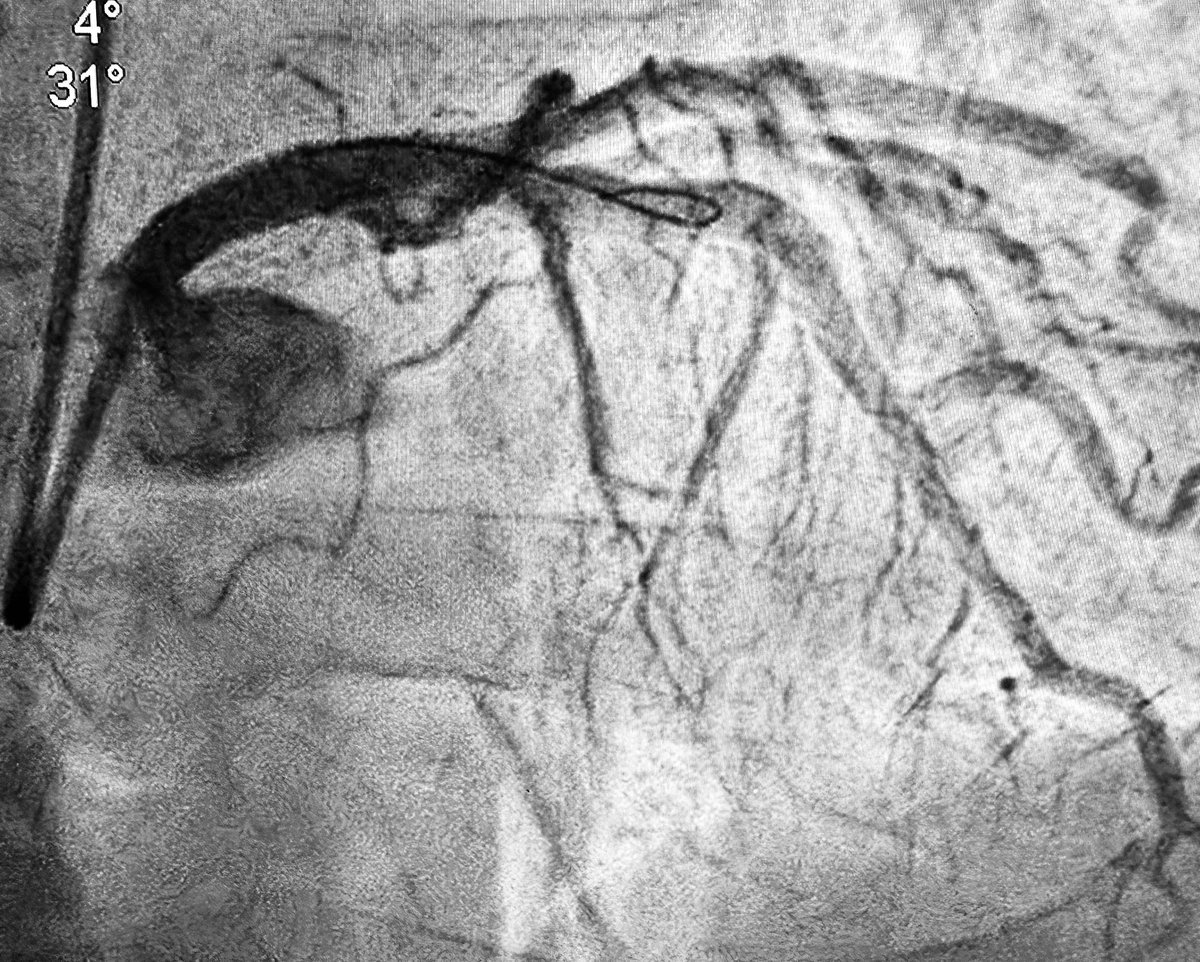

👍I’d say there is (at least) equipoise here (with IVI-guidance/optimization and dz not involving the trifurcation) re: #PCIvsCABG (LM Megatron DES: 5.3 mm distal to 6.0 mm ostial [with already-in-place IABP: removed post-PCI]): 🔗 jacc.org/doi/10.1016/j.……